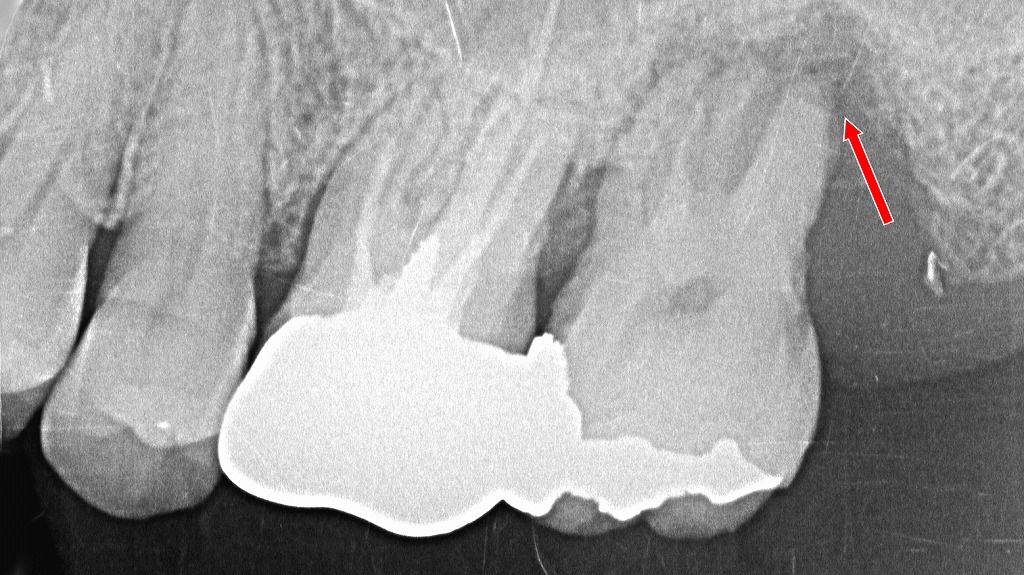

赤矢印の部位では、歯の根の先端(根尖)まで歯槽骨が大きく吸収しており、歯を支える力が大きく失われています。このような重度歯周病では、歯の動揺が強く、矯正治療を行っても安定性が得られないため、抜歯が適切と判断されるケースです。